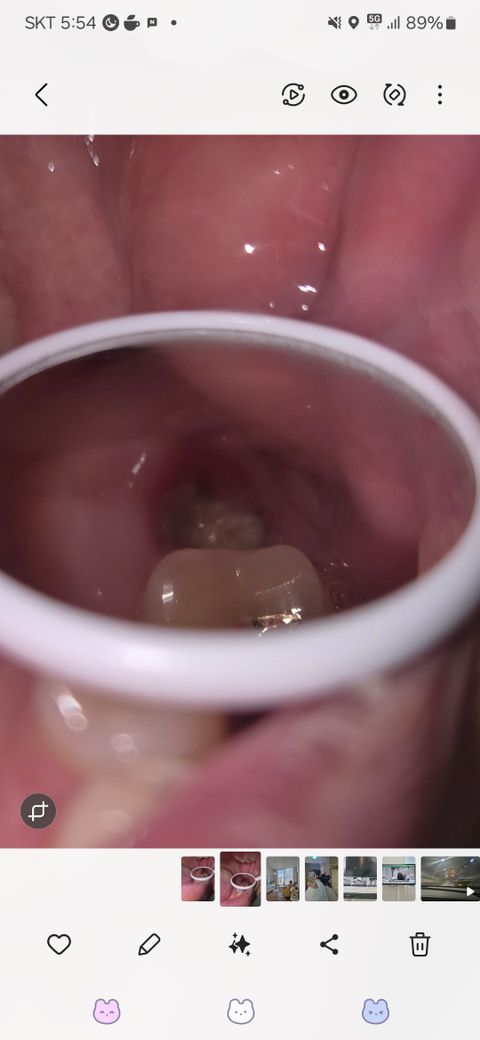

상악 어금니 발치후 노란덩어리 염증일까요?

상악 어금니발치하고 2주되었습니다.

치경으로 보니 구멍안에 저렇게 노란 덩어리가 생겼는데,염증 증상일까요??

• 1번 째 사진

정상적으로 아물고 있습니다. 잇몸 부위에 하얗게 딱지 앉은 것으로 보면 됩니다. 밑에서 살이 차올라 오면 없어집니다.